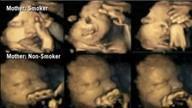

איך מגיב העובר לעישון של האם בהריון?

מערכת אינפומד מאת: מערכת אינפומד 24/03/2015

• כתבה מכילה וידיאו

מחקר חדשני מצא כי ניתן לראות כבר באולטרסאונד שוני בין עוברים לאמהות מעשנות – לאלו שלא. החוקרים: מצאנו שעישון גורם ל... לכתבה המלאה